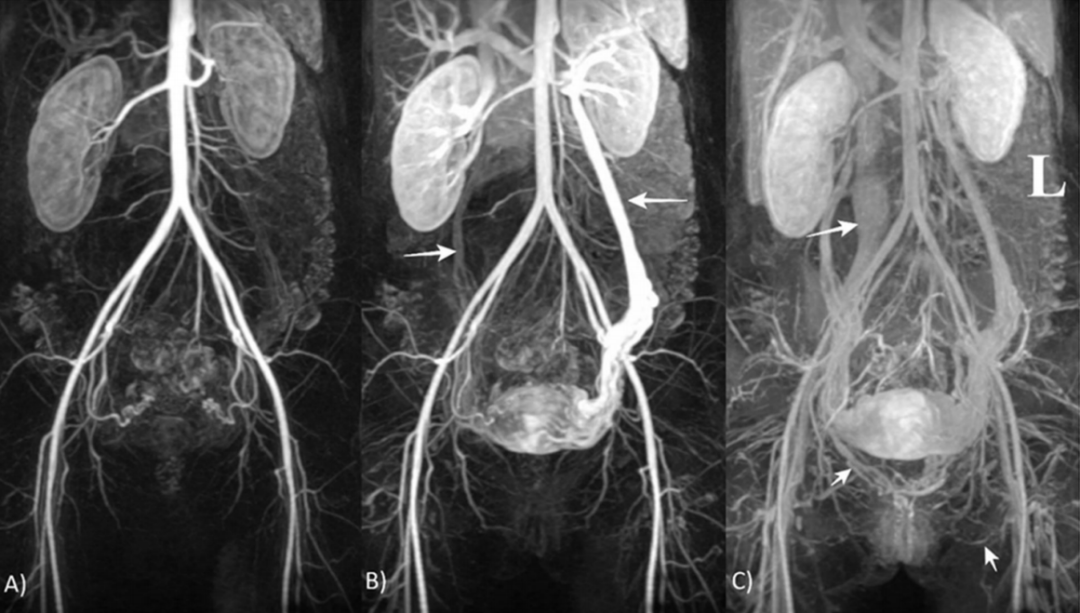

图:磁共振血管成像(TR-MRA):静脉注射造影剂,腹部和盆腔血管系统动态成像。(A)动脉期;(B)静脉期,箭头示卵巢静脉;(C)静脉晚期可见下腔静脉,箭头示右外阴内静脉和左闭孔静脉